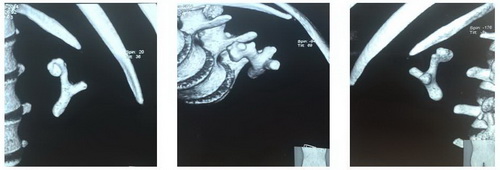

Рис. Обзорная рентгенография и мультиспиральная компьютерная томография.

Рис. Рентгенологические этапы операции.